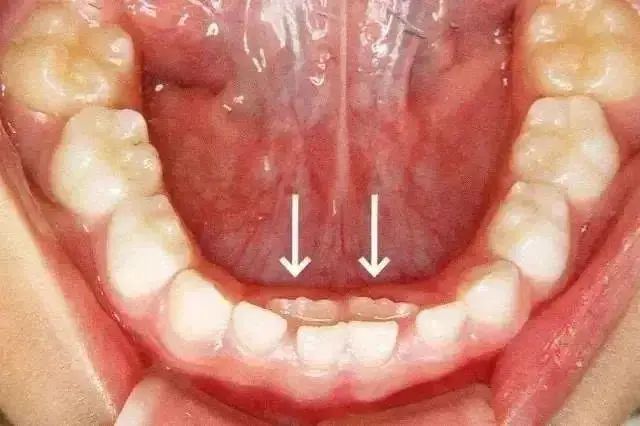

乳牙滞留是指恒牙相继长出,乳牙未能及时脱落。或者恒牙未萌出,保留在恒牙列中。乳牙的脱落与恒牙的生长之间存在着密切的关系。这种情况多见于换牙期的下颌门牙,恒牙长在舌侧,乳牙留于唇侧,出现双排牙。

三、双排牙一定要拔吗?

很多家长看到孩子“双排牙”后非常着急,要求医生赶紧拔掉,这样对吗?

过早过多的拔牙,容易造成孩子牙颌畸形,拔不拔牙首先要看恒牙萌出的高度,当恒牙只萌出 1/3 或者 2/3 ,且前排牙齿还没有松动的情况下,建议家长先让孩子多吃硬性食物,比如啃苹果、玉米等,促进自然脱落。